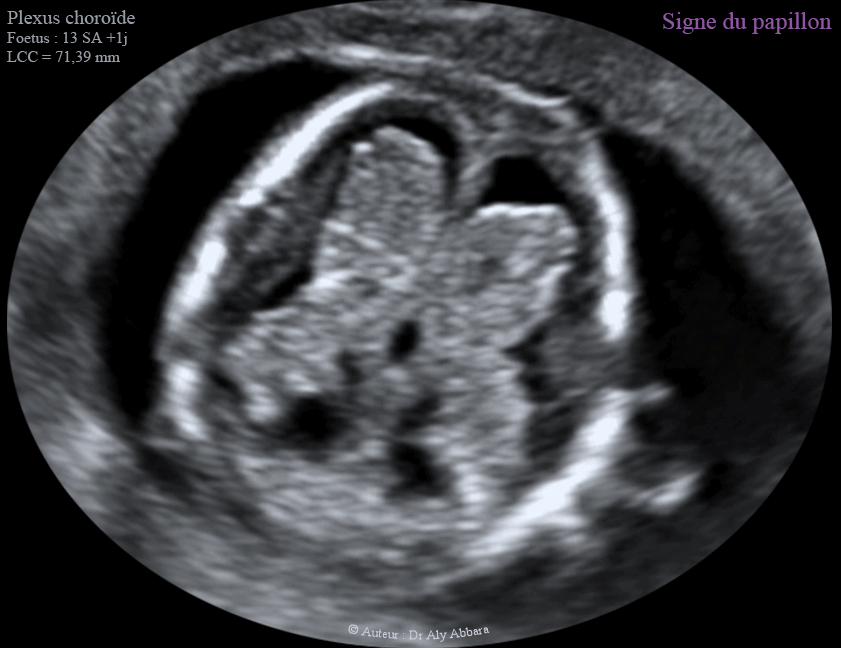

Les plexus choroïdes et le signe du papillon - 12 - 13 SA - الضفائر المشيمية في الدماغ وعلامة الفراشة

Les deux plexus choroïdes et le signe du papillon - 12 - 13 SA - الضفائر المشيمية في الدماغ وعلامة الفراشة

Le signe du papillon

Un signe échographique permettant d'exclure le diagnostic de l'holoprosencéphalie alobaire au cours du premier trimestre de la grossesse :

• Au cours du premier trimestre de la grossesse, entre 11 et 14 SA, les deux plexus choroïdes normaux occupent largement les deux ventricules latéraux et composent ensemble une forme ressemblant à un papillon "signe du papillon - Butterfly sign" ; ce signe est absent dans l'holoprosencéphalie alobaire.

• En cas d'holoprosencéphalie alobaire, on peut observer la présence d'un ventricule unique au lieu des deux ventricules latéraux du cerveau, puis l'apparence anormale des plexus choroïdes : absence du " signe du papillon "